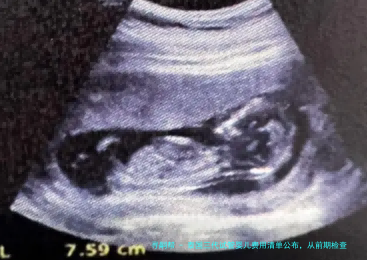

取出的卵子与精子在试管受孕后,会形成受精卵,并被培养成胚胎。对于三代试管婴儿而言,胚胎培育到囊胚阶段,然后进行基因学筛选(PGT/PGS/PGD)是必不可少的环节。